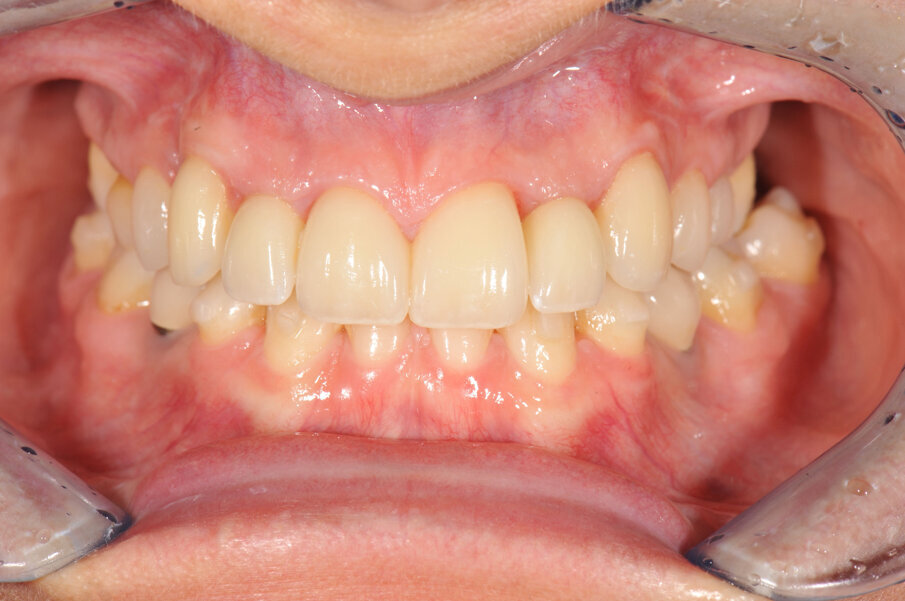

Door de regulatie van de cuspidaten naar distaal is botappositie opgetreden, waardoor bij het plaatsen van de twee implantaten een minimale botopbouw volgens een GBR-techniek noodzakelijk was (afbeelding 7-9). Via digital smile design werd de uiteindelijke vorm gesimuleerd (afbeelding 10 en 11). Er werden twee verschroefde zirkonium kronen met opgebakken porselein vervaardigd voor de implantaten en er werden facings van lithiumdisilicaat gemaakt bij de centrale incisieven en cuspidaten (afbeelding 12-17).